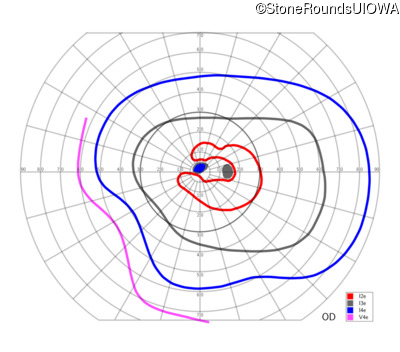

This 52 year old man had normal vision until his mid 30's when he began to have trouble distinguishing colors. the issuing 10 years he had a gradual loss of visual acuity accompanied by increasing photophobia.

| Age at visit: 55 years |

| Age at visit: 58 years |

| Age at visit: 61 years |

| Age at visit: 64 years |